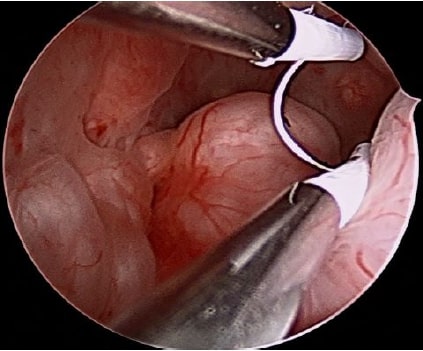

Hysteroscopy is used in infertility treatment to directly visualize and diagnose intrauterine abnormalities like fibroids, polyps, and adhesions that can hinder embryo implantation and reduce IVF success rates. It also serves as a treatment to remove these issues, providing a healthy environment for potential pregnancy by correcting conditions such as septums and submucosal fibroids.

It plays a vital role in infertility management by directly visualizing and treating abnormalities within uterine cavity, such as polyps, fibroids, and adhesions which can impede embryo implantation and pregnancy. It serves as a diagnostic tool to identify these issues, especially when other tests are inconclusive, and a therapeutic approach to correct them in a single procedure. This "see and treat" capability helps create a healthier uterine environment, improving the chances of successful embryo implantation and a positive fertility outcome, particularly in IUI & IVF cycles.

Hysteroscopy plays a crucial role in improving the success of  in vitro fertilization (IVF).

- Pre-IVF assessment: . Treating any identified abnormalities can increase the chances of successful embryo implantation and a higher clinical pregnancy rate.

- Recurrent implantation failure (RIF): For patients with a history of failed IVF cycles, hysteroscopy is highly recommended to re-evaluate the uterine cavity. This can reveal subtle or previously missed issues that may be contributing to implantation failure.